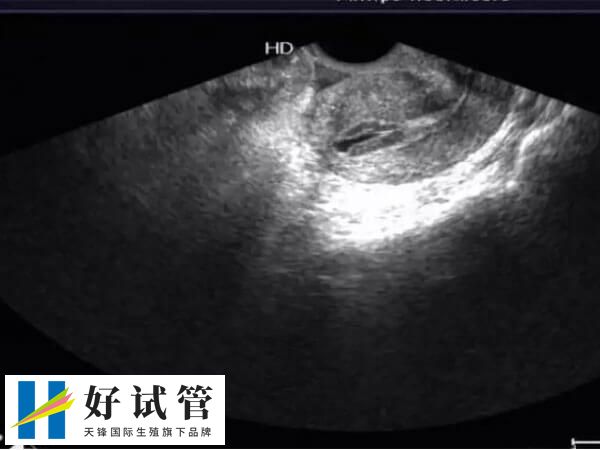

在进行试管婴儿治疗前,医生会对夫妇进行全面检查。这些检查包括血液检查、精液分析、内分泌检查、卵巢B超等。通过这些检查可以了解夫妇的身体状况和生育障碍原因,并制定针对性的治疗方案。

在取卵前,医生会给女性注射控制卵巢功能的药物。在给药过程中需要严格监测女性的卵泡大小和数量,并根据监测结果调整药物剂量和使用时间。通过精密控制药物剂量可以最大程度地避免并发症和提高取卵成功率。